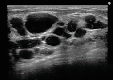

- しこり除去

- 他院の施術による脂肪注入

のしこりをエコーで確認して、

確実に除去します。